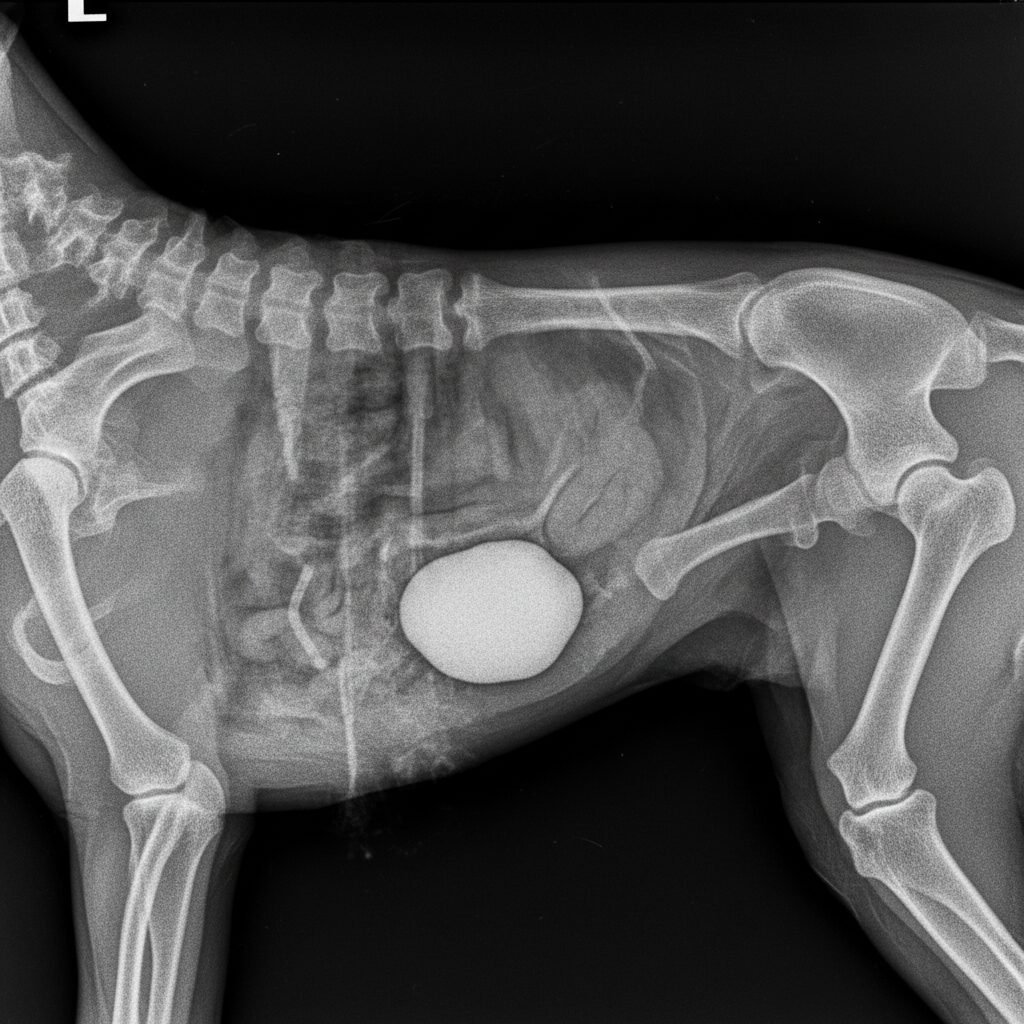

- Imaging: This is the most definitive step for diagnosing an obstruction. X-rays are excellent for visualizing dense objects like rocks. In some cases, an ultrasound may be used to get a better look at the gastrointestinal tract and surrounding organs.